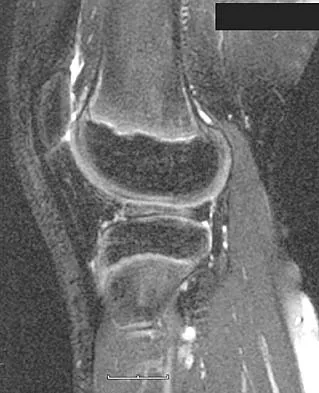

A 28-year-old professional dancer reports a 3-month history of progressive pain in the posterior aspect of the left ankle. Her symptoms are worse when she assumes the en pointe position. Examination reveals tenderness to palpation at the posterolateral aspect of the ankle posterior to the peroneal tendons which is made worse with passive plantar flexion. There is no nodularity, fluctuance, or tenderness of the Achilles tendon. The neurovascular examination is unremarkable. A lateral radiograph and MRI scan are shown in Figures 16a and 16b, respectively. Management should consist of

The imaging studies reveal findings typical of the os trigonum syndrome. This condition results from inflammation between the os trigonum and the adjacent talus. The symptoms of posterior ankle pain are exacerbated by plantar flexion, which stresses the fibrous union between these two bones. Definitive management of the high-level athlete involves excision of the os trigonum from a medial approach, although arthroscopic excision has also been described. The os trigonum is not an intra-articular structure; therefore, ankle arthroscopy is neither diagnostic nor therapeutic. Abramowitz Y, Wollstein R, Barzilay Y, et al: Outcome of resection of a symptomatic os trigonum. J Bone Joint Surg Am 2003;85:1051-1057. Mouhsine E, Crevoisier X, Leyvraz P, et al: Post-traumatic overload or acute syndrome of the os trigonum: A possible cause of posterior ankle impingement. Knee Surg Sports Traumatol Arthrosc 2004;12:250-253.